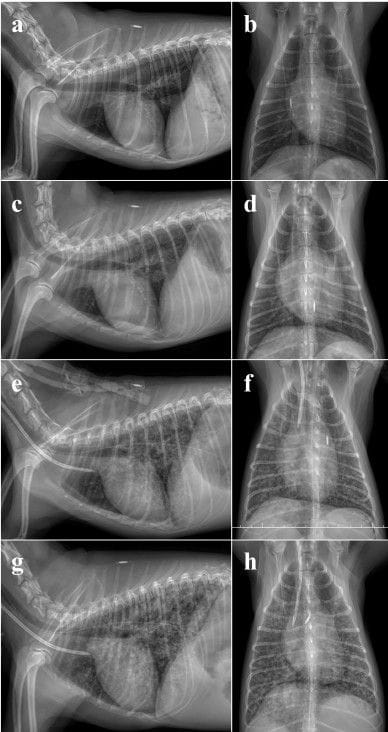

Following initiation of haemodialysis, the dog developed acute tachypnoea and progressive bilateral pulmonary infiltrates consistent with noncardiogenic pulmonary oedema. Despite improvement in biochemical parameters after dialysis, respiratory abnormalities persisted initially. After three haemodialysis sessions, urine output improved to polyuria and uraemia decreased. Pulmonary infiltrates gradually resolved radiographically by Day 7 and completely by Day 18, with clinical resolution of tachypnoea by Day 12.

2Sequential radiographic evaluation of a 7-year-old female dog diagnosed with acute kidney injury (AKI) from Days 0 to 3. Lateral and ventrodorsal views were taken. (a, b) On Day 0, when diagnosed with AKI, no significant findings were detected in the thoracic radiographs, including the heart and lungs. Localised high-density foci in the lungs indicated pulmonary osteoma. (c, d) On Day 1, early pulmonary changes of mild interstitial infiltration were noted in the bilateral caudal lung lobes, causing a slightly indistinct margin of the pulmonary vasculature. (e, f) The radiographs of Day 2, post-dialysis imaging, revealed progression of pulmonary changes, showing a marked increase in the bronchointerstitial pattern along with diffuse alveolar infiltrates in the bilateral caudal lobes, obscuring the margins of the heart and pulmonary vessels. The presence of an oesophageal tube in the cervical region was found. The patterns and distribution of lung infiltrates indicated uraemic pneumonitis with noncardiogenic pulmonary oedema. (g, h) On Day 3, extensive pulmonary infiltration was observed throughout the lung fields, indicating a widespread involvement